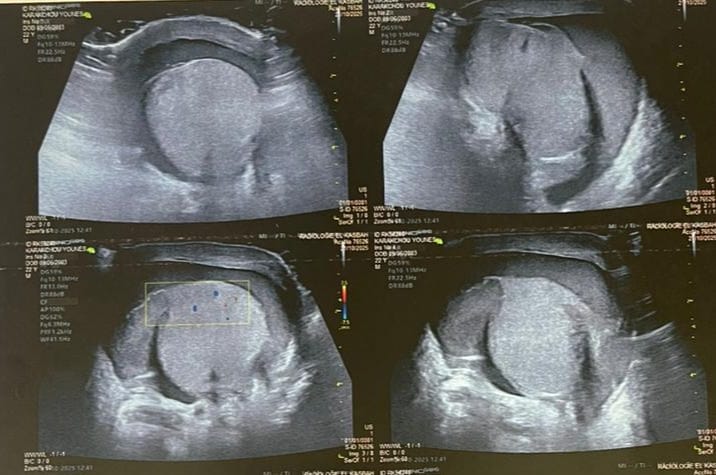

Figure 1: Ultrasound images showing testicular enlargement with a heterogeneous intraparenchymal hematoma and a breach in the tunica albuginea, consistent with testicular rupture.

Clinically, pain was present in all patients. Scrotal swelling was observed in 90% of cases, and scrotal wounds were characteristic of open injuries. Scrotal hematoma was present in 90% of cases, whereas hematocele was noted in only 30%. Scrotal ultrasonography was performed in 75% of patients, revealing scrotal hematoma in 17 cases and tunica albuginea rupture in 6 cases.